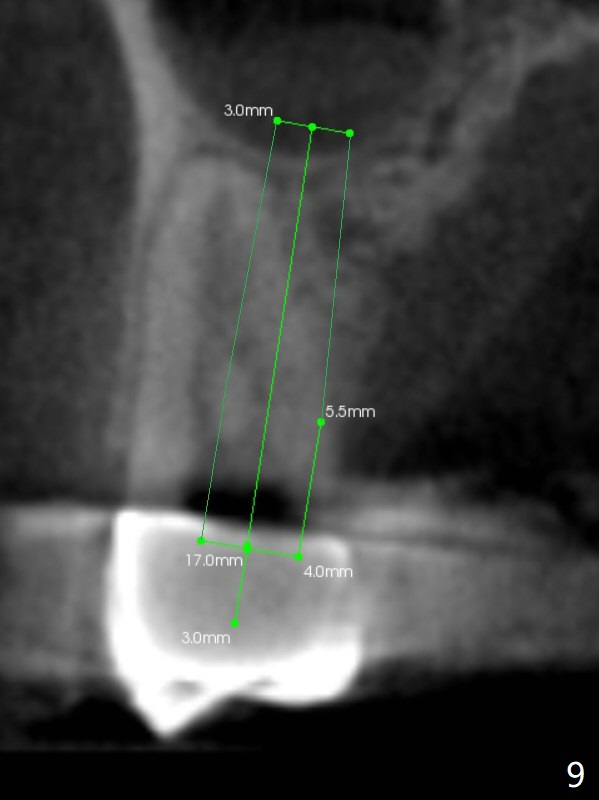

A 64-year-old man requests implant restoration after the upper FPD dislodges (Fig.1). The measurement of the septal height at #2 by PA (Fig.2) is not as precise as CBCT (Fig.11, taken 4 years earlier). There appears to be 2.8 mm bone apical to the tooth #4 (Fig.2); in contrast, the bone is more or less buccal and palatal to the root apex shown by CT (Fig.5). Furthermore CT more clearly shows apical lesions of the tooth #5 (Fig.3,4) than PA (Fig.2). In addition to pulpal test, RCT should be done for #5 prior to implant placement at #4.

After extraction of the tooth #4, osteotomy is initiated in the middle of the palatal slope (Fig.6), followed immediately by change in trajectory (Fig.7). The depth of the osteotomy is ~ 5 mm (Fig.8), followed by 2.8 mm round bur from Sinus Lift Master Kit. Press the burs palatally. Following Vanilla Graft (red circles), place a 3.5 or 4.0x17 mm dummy and final implants (Fig.3,9,10).